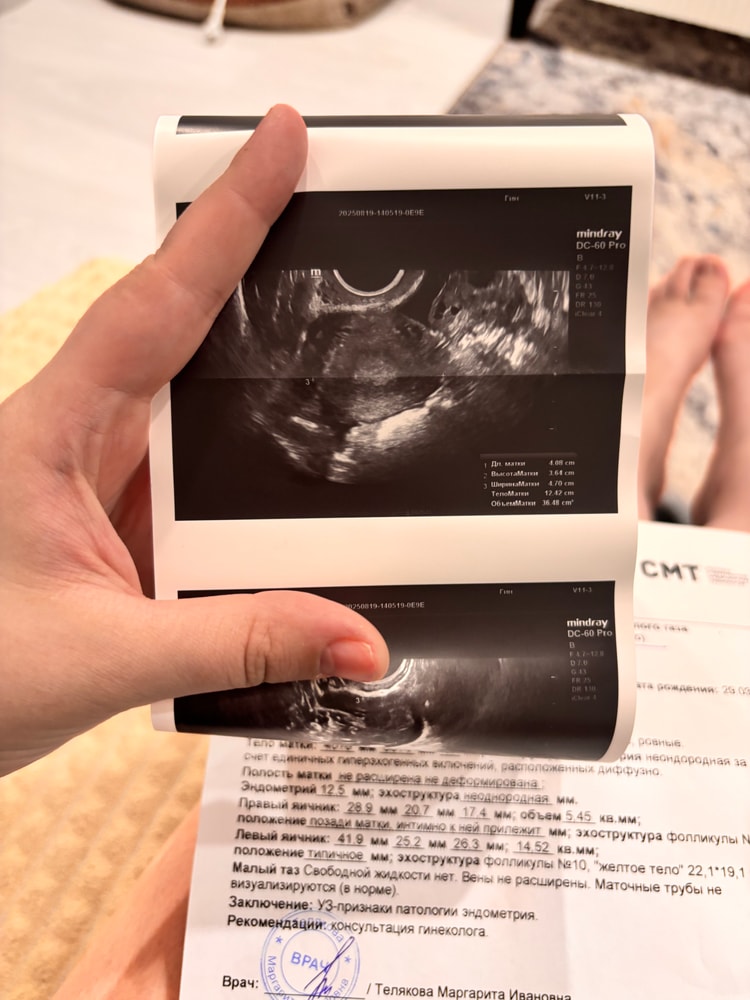

на узи поставили под вопросом полип эндометрия, это он? Ещё сказали, что имеется спаечный процесс в малом тазу…

отправили на гистероскопию